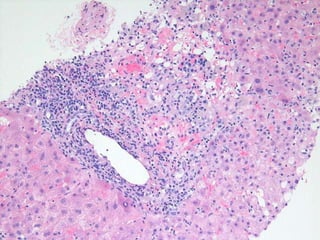

LS08-10290 Abnormal LFT, negative for Hepatitis A, B, C.  Sono: heterogeneous liver.

BS09-10453:  Dx: Chronic hepatitis, with severe activity (focal parenchymal collapse) and cirrhosis, suggestive of autoimmune hepatitis. Corresponds to: Modified Ishak stage 4/4 Metavir F4

LS08-10290 Abnormal LFT,negative for Hepatitis A, B, C. Sono: heterogeneous liver.

BS09-10453: Dx:Chronic hepatitis, with severe activity (focal parenchymal collapse) and cirrhosis, suggestive of autoimmune hepatitis. Corresponds to: Modified Ishak stage 4/4 Metavir F4